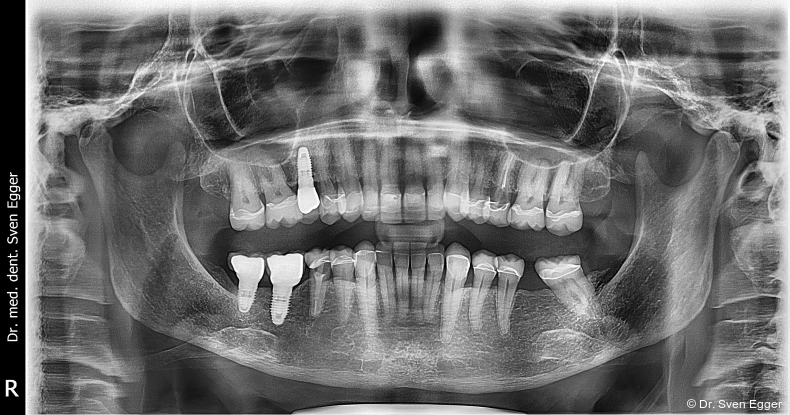

Das OPG zeigt insuffiziente endodontische Versorgungen an 15, 25 und 46. Die Kieferhöhle rechts zeigt eine kirschgroße, kugelige Verschattung (Überweisung/Abklärung Kieferchirurgie).

- Einzelzahnimplantate 047 und gegebenenfalls bei 15, 25 und 46 (bei erfolgloser WB-Revision).

Die mit einem Restrisiko behafteten Zähne 15 und 46 (Zahn 15 zeigte nach Revision noch immer eine leichte Drucksymptomatik, bei Zahn 46 waren die mesialen Wurzelkanäle obliteriert) erwiesen sich in der Vorbehandlung dann als nicht erhaltungswürdig und wurden nach Extraktion durch Einzelzahnimplantate ersetzt. Alternativ hätte im 1. Quadranten die Schaltlücke Regio 15 mit einer festsitzenden Brücke geschlossen werden können. Aufgrund des ausreichenden Knochenangebotes und der besseren Mundhygienefähigkeit entschied sich die Patientin jedoch für den implantatgetragenen Einzelzahnersatz. Eine herausnehmbare Versorgung lehnte die Patientin bereits im Vorfeld ab. Die Schaltlücke im 3. Quadranten konnte im Rahmen der prothetisch/funktionellen Rehabilitation in ZKP belassen werden, da eine Antagonistenabstützung an 26 mesial und distal realisiert werden konnte. Alternativ wäre eine kieferorthopädische Distalisierung (Lückenöffnung) mit Einzelzahnimplantat 036 denkbar gewesen. Der erhöhte Behandlungs- und Zeitaufwand stand aus Sicht des Behandlers jedoch nicht im Verhältnis mit dem daraus resultierenden Nutzen. Einem regelmäßigen Recall steht die Patientin sehr aufgeschlossen gegenüber.

Die Follow-up-Untersuchung zeigte ein Ergebnis, mit dem die Patientin nach 15 Jahren Tragezeit weiterhin vollumfänglich zufrieden ist. Die keramische Teilkrone an Zahn 17 wurde am 31.5.2022 aufgrund Debondings nach erneuter Konditionierung wieder eingesetzt. Die Kieferhöhlen sind verschattungsfrei und zeigen keine Anzeichen eines Rezidivs der in 2007 erfolgten Zystenoperation in der rechten Kieferhöhle (Mukozele). Die endodontisch revidierten Zähne 25 und 45 zeigen weder klinisch noch röntgenologisch Auffälligkeiten. Die Stellung der Ober- und Unterkieferfront sowie die in ZKP etablierte horizontale und vertikale Relation des Unterkiefers ist stabil und bereitet keinerlei Schwierigkeiten. Die Implantate weisen klinisch und röntgenologisch schöne Hart- und Weichgewebsverhältnisse auf. Die häusliche Mundhygiene ist sehr gut. Es sind keine Anzeichen einer Funktionsproblematik zu erkennen. Die Michigan-Schiene wurde 2022 erneuert. Für die vorliegende Situation lässt sich damit auch weiterhin eine sehr gute Langzeitprognose aussprechen (Abb. 18–25).